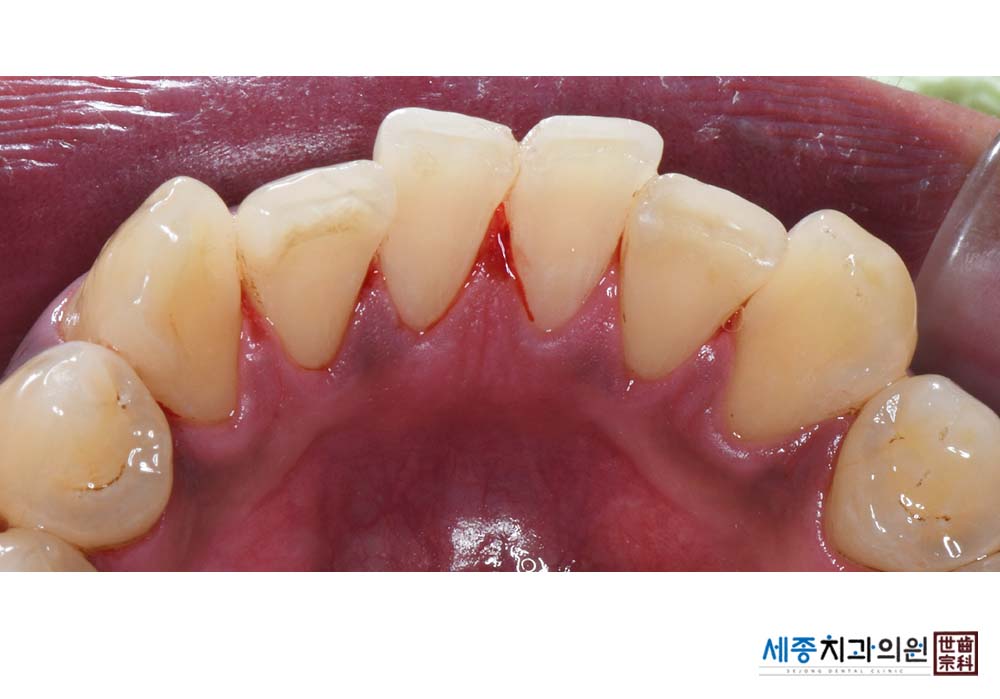

[스케일링] 치주질환 예방 스케일링

치료후 : 2023-02-20

가글마취&저주파 스켈러를 사용한 스케일링